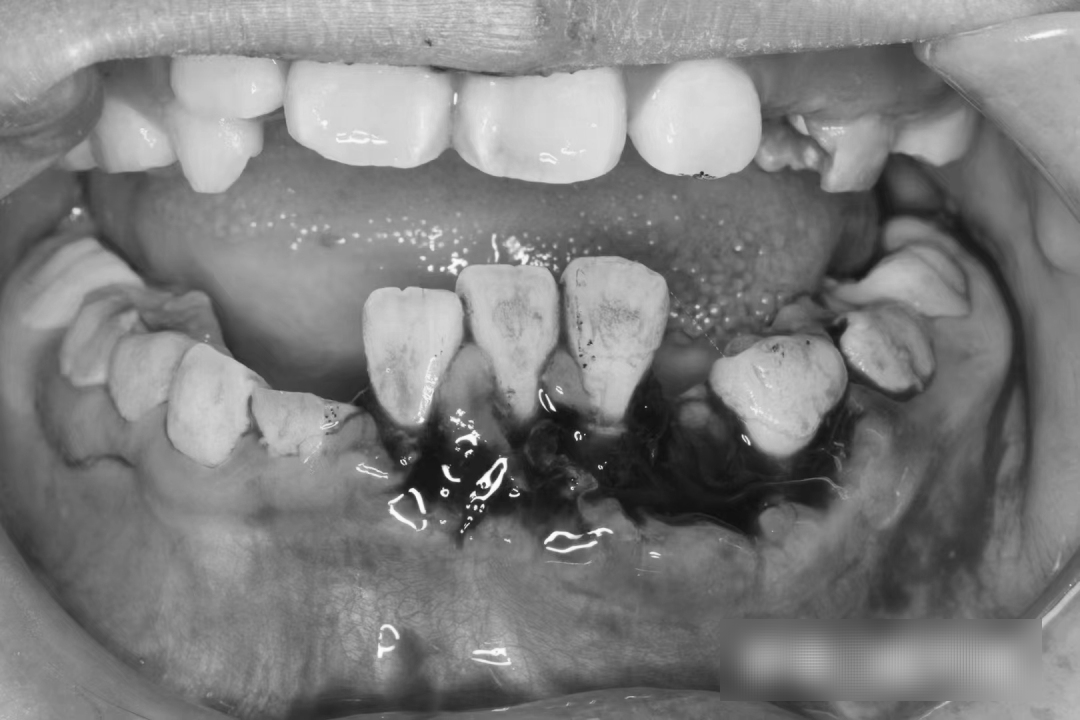

“我女儿说,骑电动车的是一名妇女,她被撞倒后对方问她有没有事,孩子当时有点疼,也被吓懵了,呆呆地说了句没事,对方竟直接走了。尽管路过的好心人建议该妇女给孩子买瓶水,看看嘴巴和牙齿,对方也没照做。”王先生气愤地说,他把孩子带到专业的牙科诊所拍了片子,两颗虎牙,一颗直接摔断了,另一颗被连根拔起不见了,三颗门牙牙根受损严重,需要矫正。